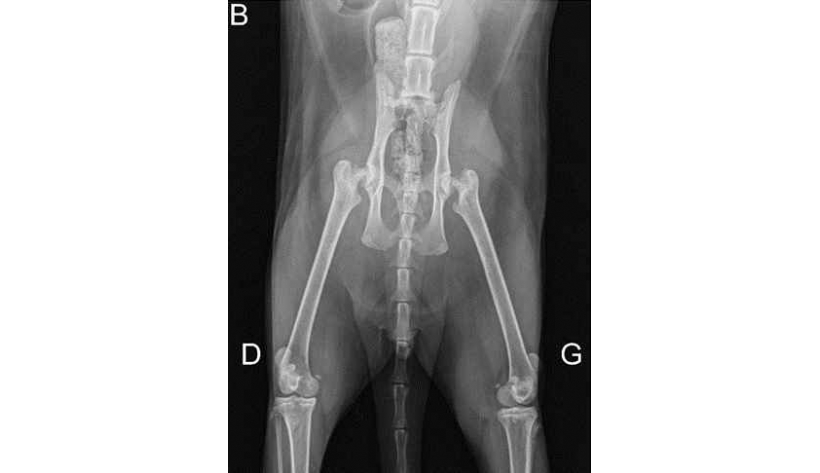

Mercredi 6 Novembre 2024 Animaux de compagniePhoto n° 1A : Radiographie de face du bassin et du rachis lombosacré.

Un chat Maine coon mâle castré de 1,5 an est présenté pour l'exploration d'une boiterie marquée des membres pelviens évoluant depuis trois semaines sans traumatisme rapporté. L'examen neurologique montre une parésie et une ataxie des membres pelviens. Il ...